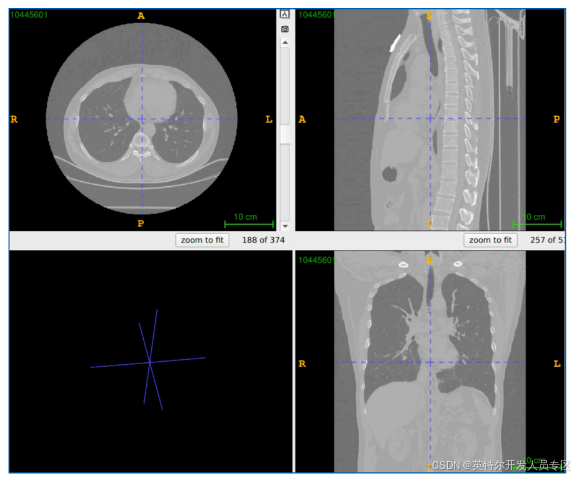

目前,多个合作伙伴已经参考基于英特尔锐炫™ 显卡的医学影像AI 推理解决方案参考设计,推出了相应的产品与方案。以汇医慧影推出的 AI 骨密度辅助检测系统为例,该系统是基于 CT 胸腹部

平扫图像数据的 CT 人工智能骨密度检测软件,可自动进行骨密度测量与分析,并同步给出椎体分析数据、椎间分析数据、腹部组织成分分析。

为了验证该方案的性能表现,汇医慧影进行了测试,受测的骨密度筛查项目共包含 4 个 AI 模型:基于 3D-Resnet-Unet 的脊椎粗分割模型、基于 3D-Unet 的脊椎分割模型、基于 3D-DenseNet

的骨密度回归模型、基于 2D-Unet 的组织分割模型,测试数据共120 例 CT 平扫数据,扫描部位包括胸部、腹部、胸腹连扫,典型测试样本示意图如图 9 所示:

测试结果显示,纯影像 AI 推理计算时间平均为 9.55 秒6。这一测试结果表明,英特尔锐炫™ A770 性能优异,可助力检测系统高效完成骨密度筛查场景中的数据测算与分析任务。

图 9. 骨密度筛查典型测试样本示意